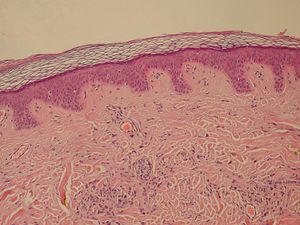

Normal Epidermis and Dermis with Intradermal Nevus 10x.JPG

Normal Epidermis and Dermis with Intradermal Nevus 10x-cropped

الورم الحميد، هو كتلة من الخلايا (ورم) التي ليس لديها القدرة على غزو أو انبثاث الأنسجة المجاورة. لا تقمم هذه الخلايا بالانتشار في الأنسجة المجاورة أو غزوها؛ إلا أنها في بعض الأحيان ما تكون كبيرة الحجم. عند إزالتها، عادة ما لا يعاود الورم في الظهور، بخلاف ما تفعله الخلايا الخبيثة أحياناً. على عكس معظم الأورام الحميدة في جميع أجزاء الجسم، فإن أورام المخ الحميدة يمكنها أن تهدد حياة المريض.[1] بصفة عامة، تتمتع الأورام الحميدة بمعدل نمو أبطأ من الأورام الخبيثة وعادة ما تكون الخلايا الورمية أكثر تمايزاً (للخلايا سمات طبيعية).[2][3][4] تكون في الغالب محاطة بسطح خارجي (غمد ليفي من نسيج ضام) أو تبقى مع الظهارة.[5] ومن أمثلة الأورام الحميدة الشائعة الشامات والأورام العضلية الملساء الرحمية.

خلايا ميلانينية وحمة